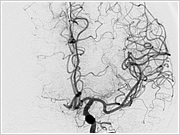

2. 血管造影検査

血管造影検査室では、主に心臓以外の血管をカテーテルで造影して診断、治療を行っていきます。

こちらの検査室では、立体的な血管像やCTのような画像を作成することができ、診断や治療の確認に利用していきます。

こちらの検査室では、立体的な血管像やCTのような画像を作成することができ、診断や治療の確認に利用していきます。

CTのような断層の画像を表示することもできます。